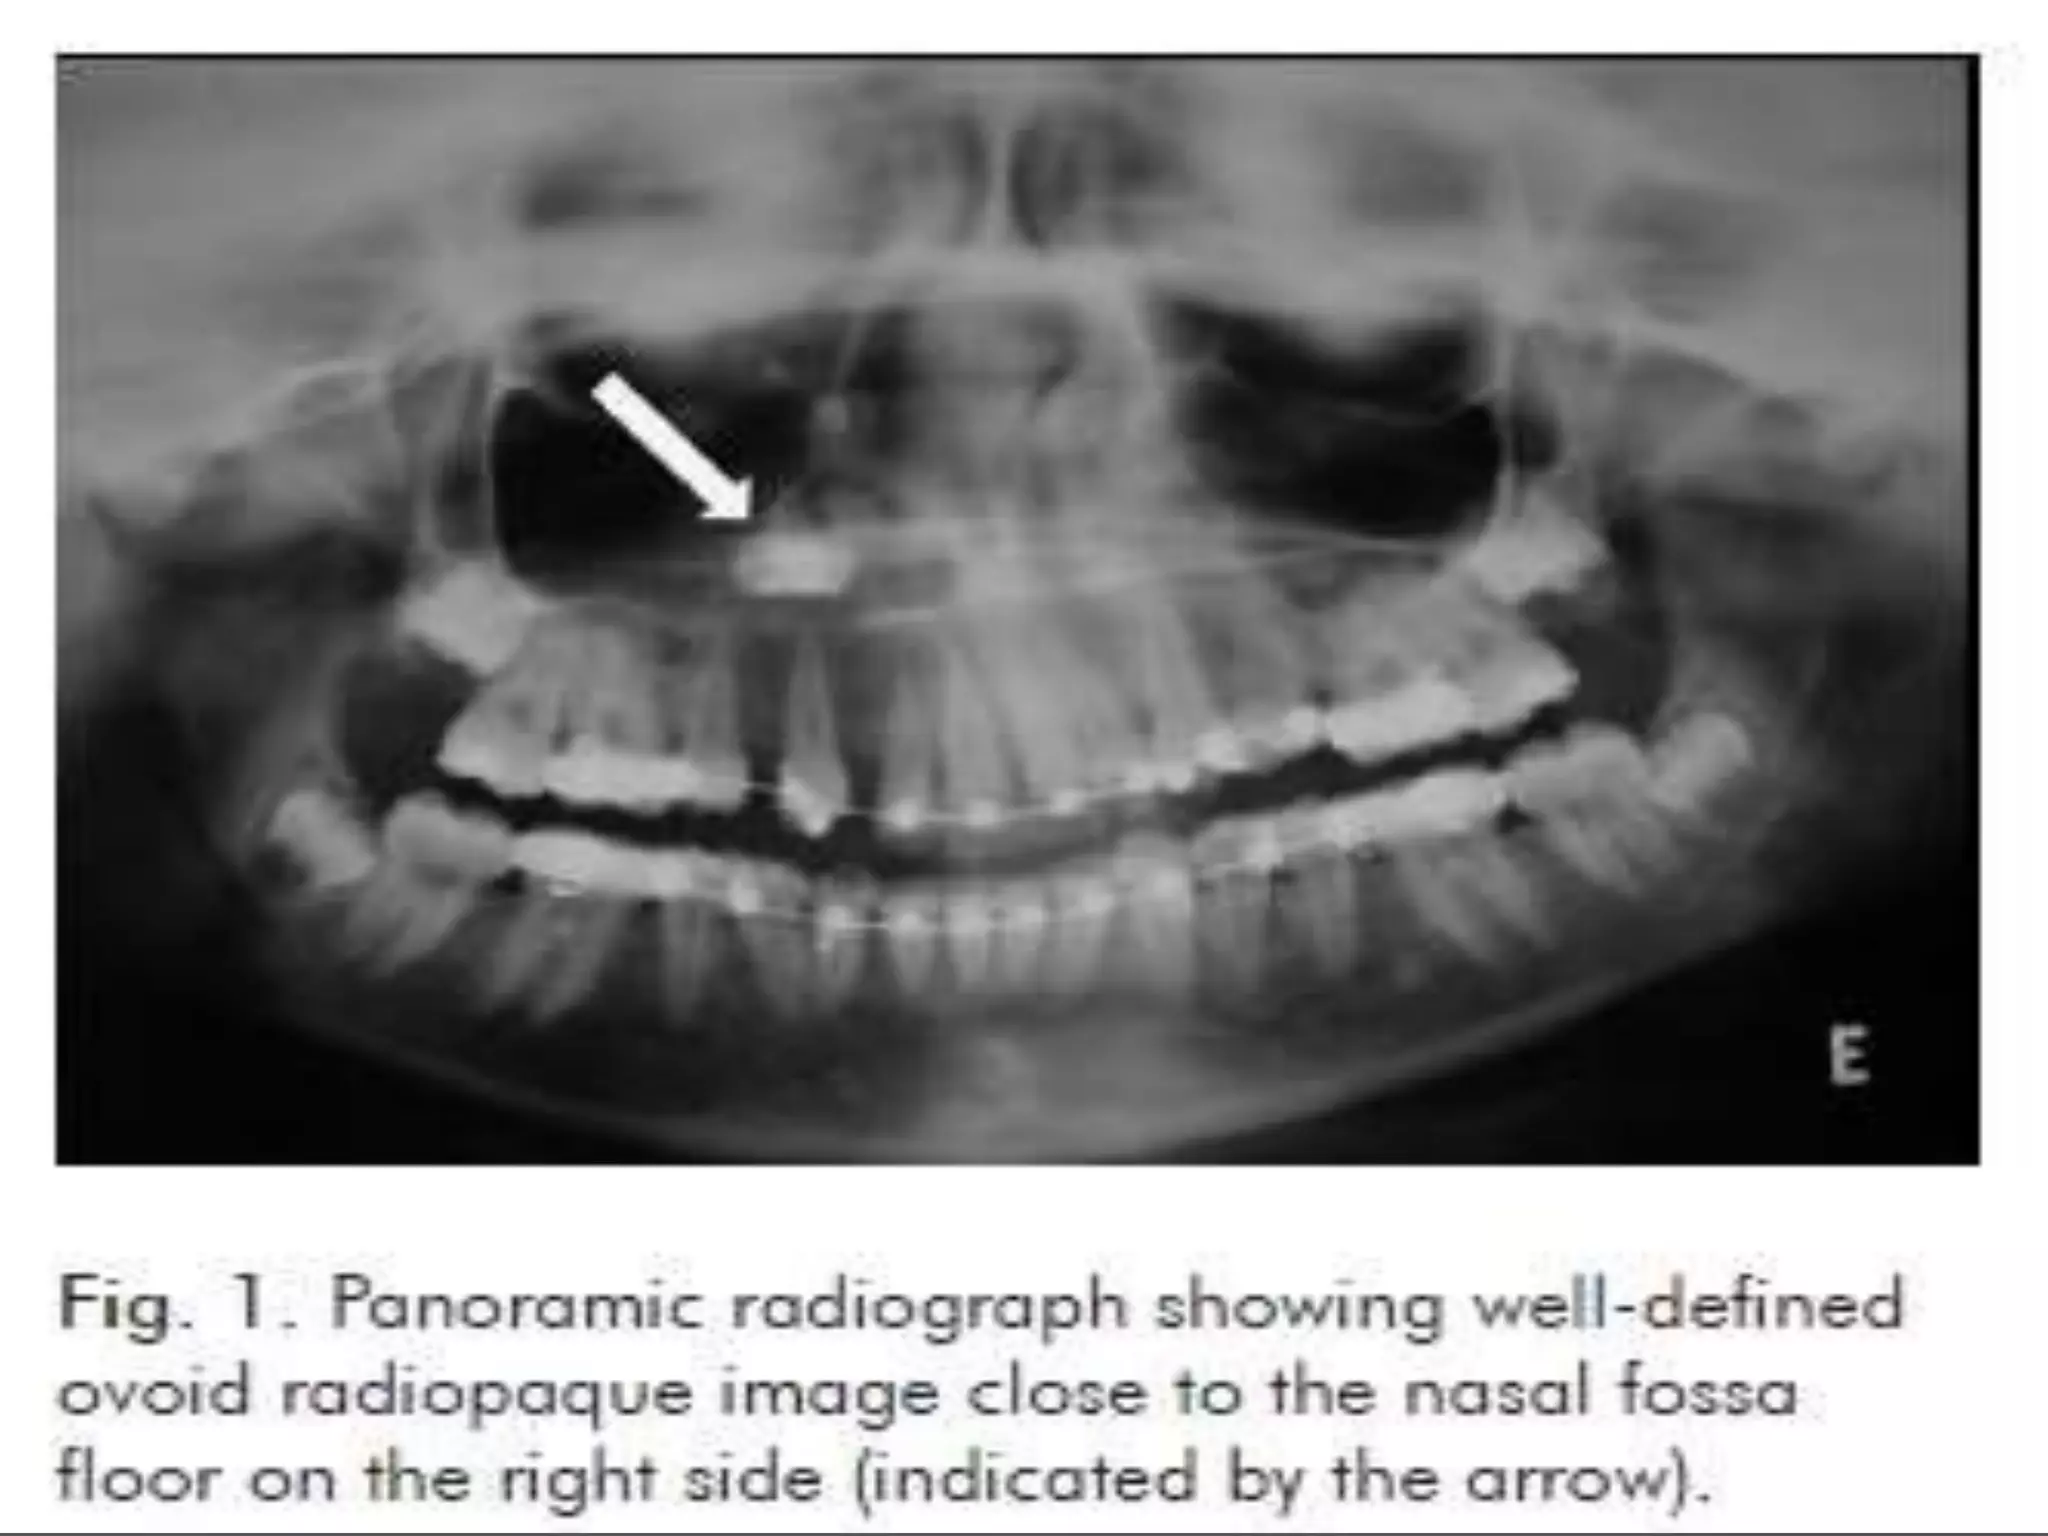

• #12 Panoramic radiograph showing a solitary, round, 3×3 cm well-defined radio-opaque mass without a radiolucent rim on the left side of the body of the mandible. The lesion extended distally of the second premolar till the mesial aspect of the second molar distal root.